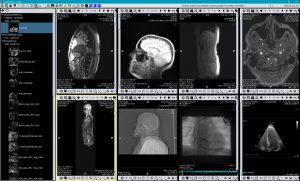

TM-PACS

TM-PACS ermöglicht die Komprimierung, Sicherung, Speicherung und Anzeige von radiologischen Bildern mit Betrachtung- und Visualiserungswerkzeugen (Zoom, Lupe, Annotation, Entfernungsmessung, Messdatenverfolgung usw.). Der Benutzer kann auch Koronarangiographie-Bilder, nuklearmedizinische PET-Bilder und klassischere Bilder (MRI, CT, Ultraschall usw.) anzeigen. Mit Hilfe von Labels, die mit den Studien verknüpft sind, können Studien gruppiert und mit einem einzigen Klick aufgerufen werden. Mit personalisierten Suchfunktionen kann die Krankenakte oder die gewünschte Studie sehr schnell gefunden werden. Die Ansicht ist für die Anzeige auf mehreren Bildschirmen optimiert. Die Integration mit der RIS- und PACS-Software, die auf den gleichen Befundworkstations installiert sind, wurde ebenfalls berücksichtigt.